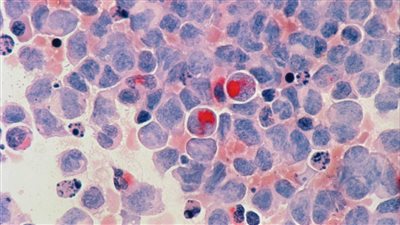

علامات سرطان الدم

أعراض غير واضحة لسرطان الدم.. انتبه

الكدمات هي علامة تنذر بالخطر لسرطان الدم